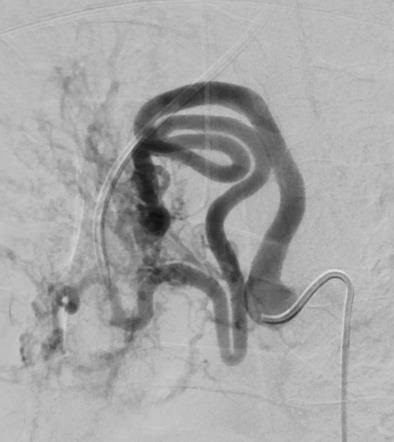

EVOH: 不一样的特性 Unique properties• 甚至可能逆血流主动分布 Active distribution even against blood stream possible

一 和NBCA,酒精血流相关被动分布相反,Onyx 逆血流主动分布 As opposed to passive, flow-related distribution (NBCA, alcohol)

一 动静脉畸形巢大于DSA所能看见的 AVM nidus is larger than visualised in DSA

AVM nidus is larger than expected in DSA

– 主动血流分布,甚至逆血流分布(血管塞和推进技术)Active distribution, even against the flow (plug & push technique)